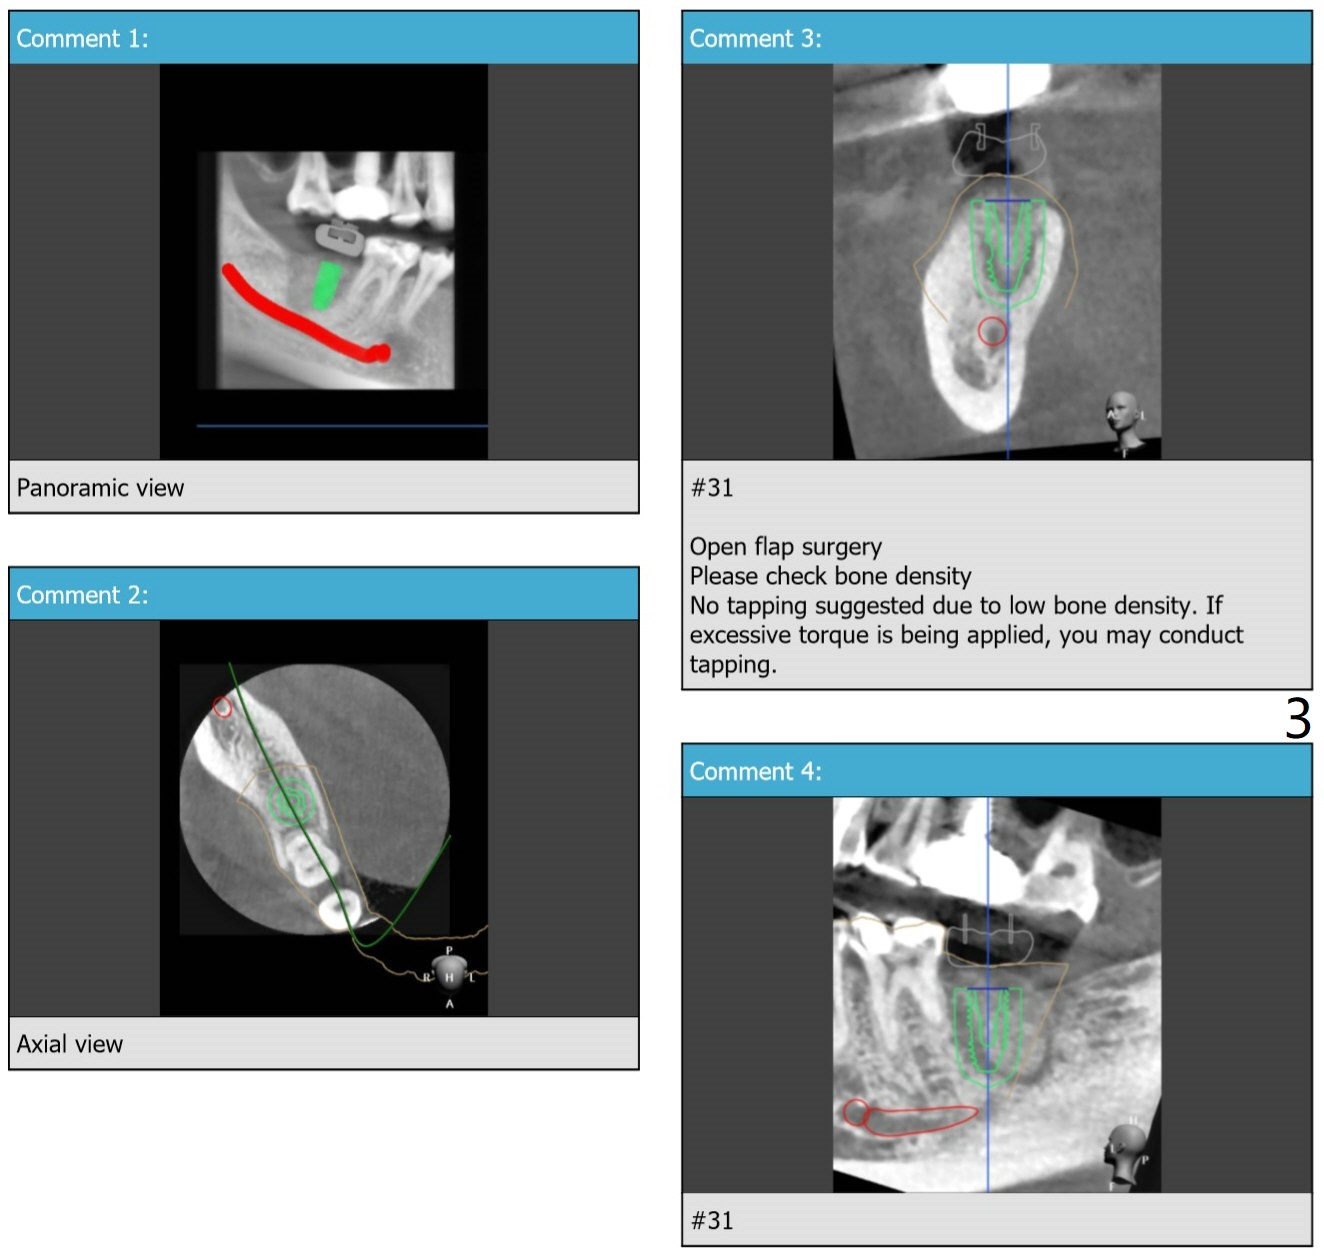

Seven months post socket preservation. Due to coronavirus, the surgery is postponed for 3 months. When the patient returns, take a PA for density check using sensor I. Also take a PA for #3 implant. Take 5x5 pre- (crestal cortex formation? (10 months post socket preservation)) and post-op.